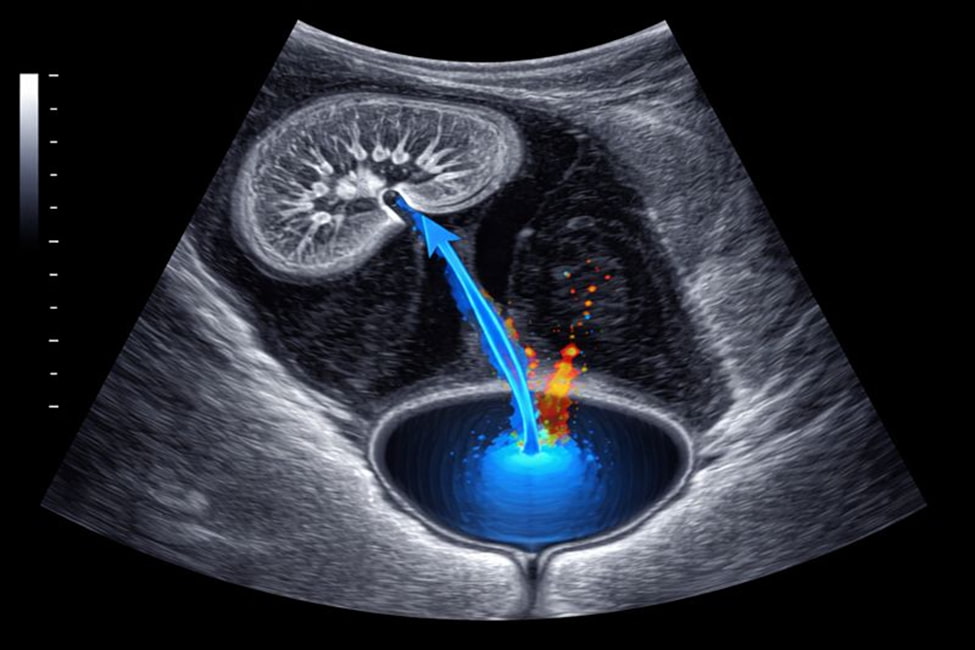

УЗИ мочевыделительной системы представляет собой неинвазивный метод инструментального исследования, при котором с помощью ультразвуковых волн визуализируются органы, участвующие в фильтрации крови и выведении продуктов обмена. Врач получает изображение в реальном времени и может оценить как форму, так и внутреннюю структуру тканей.

Обследование носит комплексный характер и охватывает такие анатомические образования, как почка, пузырь, мочеточник, различные элементы мочевыводящего тракта. В ряде случаев дополнительно оценивается надпочечник, что позволяет получить более полную клиническую картину.

УЗИ мочевыделительной системы позволяет оценить анатомические особенности и функциональное состояние органов, выявить структурные изменения и косвенные признаки нарушения оттока мочи. Врач анализирует размеры, контуры и однородность тканей.

Также УЗИ органов мочевыделительной системы помогает определить наличие расширений, уплотнений и изменений, связанных с прохождением мочи по анатомическому пути от почек к мочевому пузырю. Эти данные имеют важное значение для постановки диагноза и выбора тактики ведения пациента.